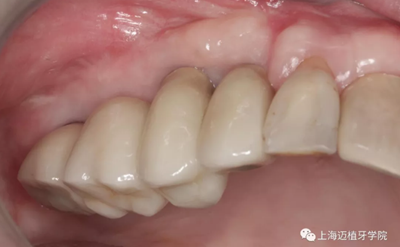

戴牙

術(shù)后全景片,骨結(jié)合良好